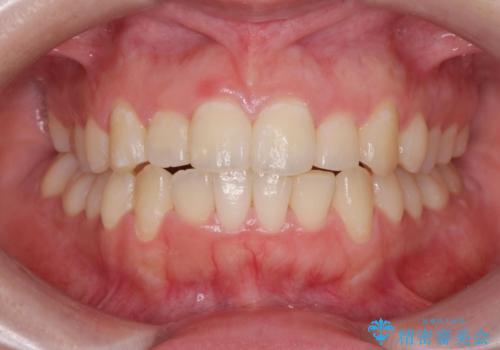

[マウスピース矯正] がたがたの歯並びをきれいにしたい

![[マウスピース矯正] がたがたの歯並びをきれいにしたいの症例 治療前](https://seimitsushinbi.jp/wp/wp-content/uploads/2025/06/0d238550c8a0fddc4de7b2c337c6c786-500x350.jpg?v=1750323380)

![[マウスピース矯正] がたがたの歯並びをきれいにしたいの症例 治療後](https://seimitsushinbi.jp/wp/wp-content/uploads/2025/06/IMG_0002-2-500x350.jpg?v=1750323305)